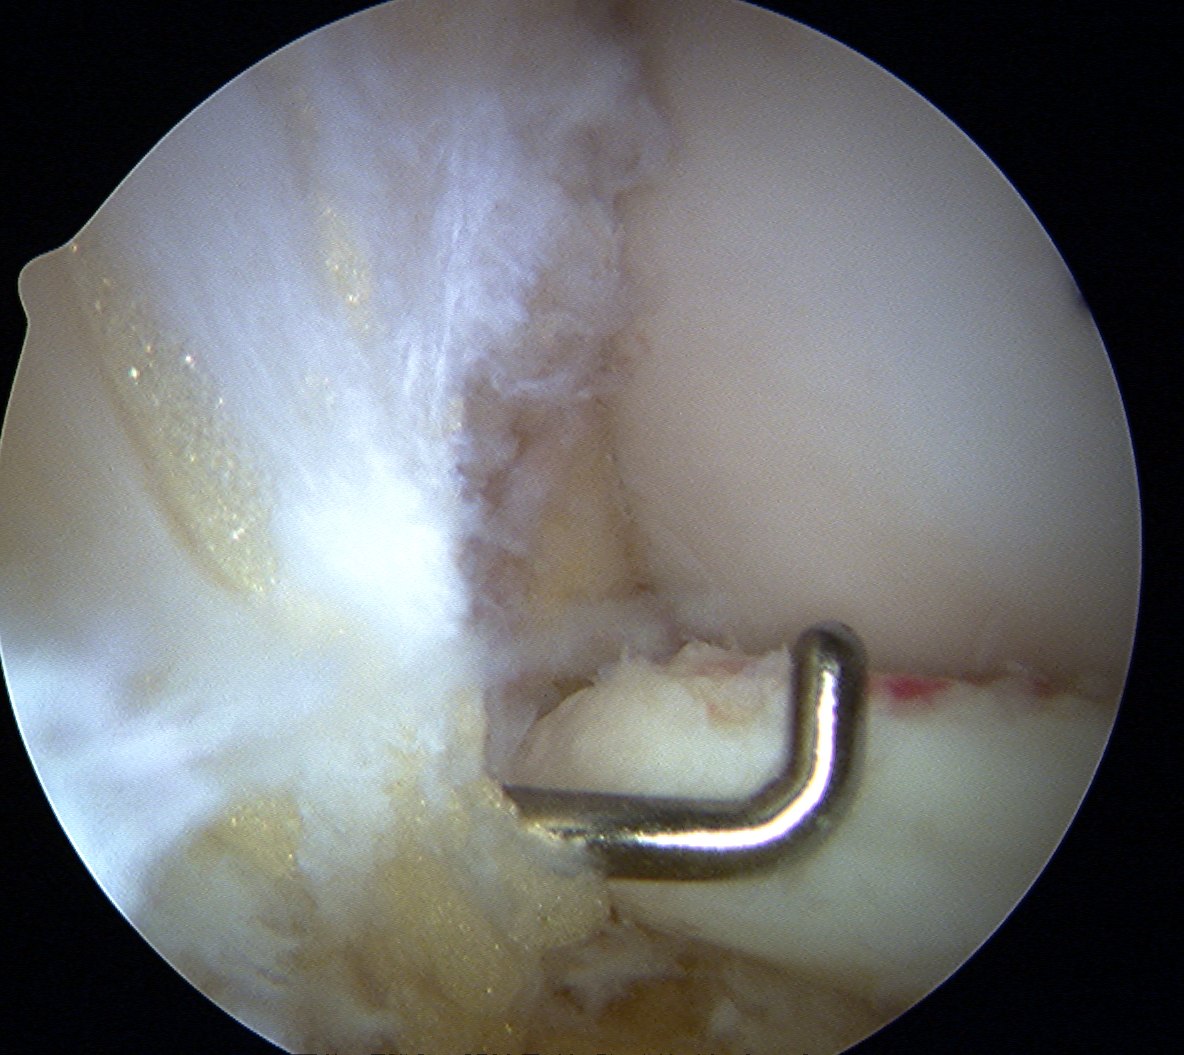

Drill site of mosaicplasty with 4.5 mm drill

- overdrill 2 - 4 mm

- do not want to leave plug proud

- impossible to sink further or remove

Insert dilator

Insertion device

- place over drill hole

- impact with hammer to seat in cartilage

- insert plug

- use tap to insert plug

- best to countersink 1 - 2 mm